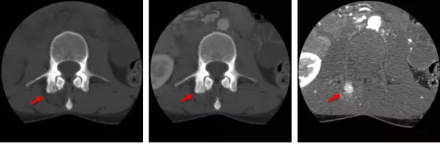

骨智能柔性減影成像功能發(fā)現(xiàn)隱匿骨占位病灶

相比傳統(tǒng)成像方式,肺部柔性減影技術(shù)通過人工智能,對(duì)平掃數(shù)據(jù)和CT肺動(dòng)脈血管掃描數(shù)據(jù)進(jìn)行智能比對(duì),解碼并識(shí)別各個(gè)器官(肺、氣管、肺動(dòng)脈、肺靜脈、主動(dòng)脈等)的空間位置,并在三維空間中進(jìn)行體素級(jí)的柔性配準(zhǔn),從而極大提升了不同序列數(shù)據(jù)的空間位置的一致性。通過肺部柔性減影技術(shù)可得到肺強(qiáng)化碘圖,可以顯示出傳統(tǒng)CTPA圖像看不到的小栓塞病變,提高了栓塞檢出率,其結(jié)果甚至可與SPECT吻合。